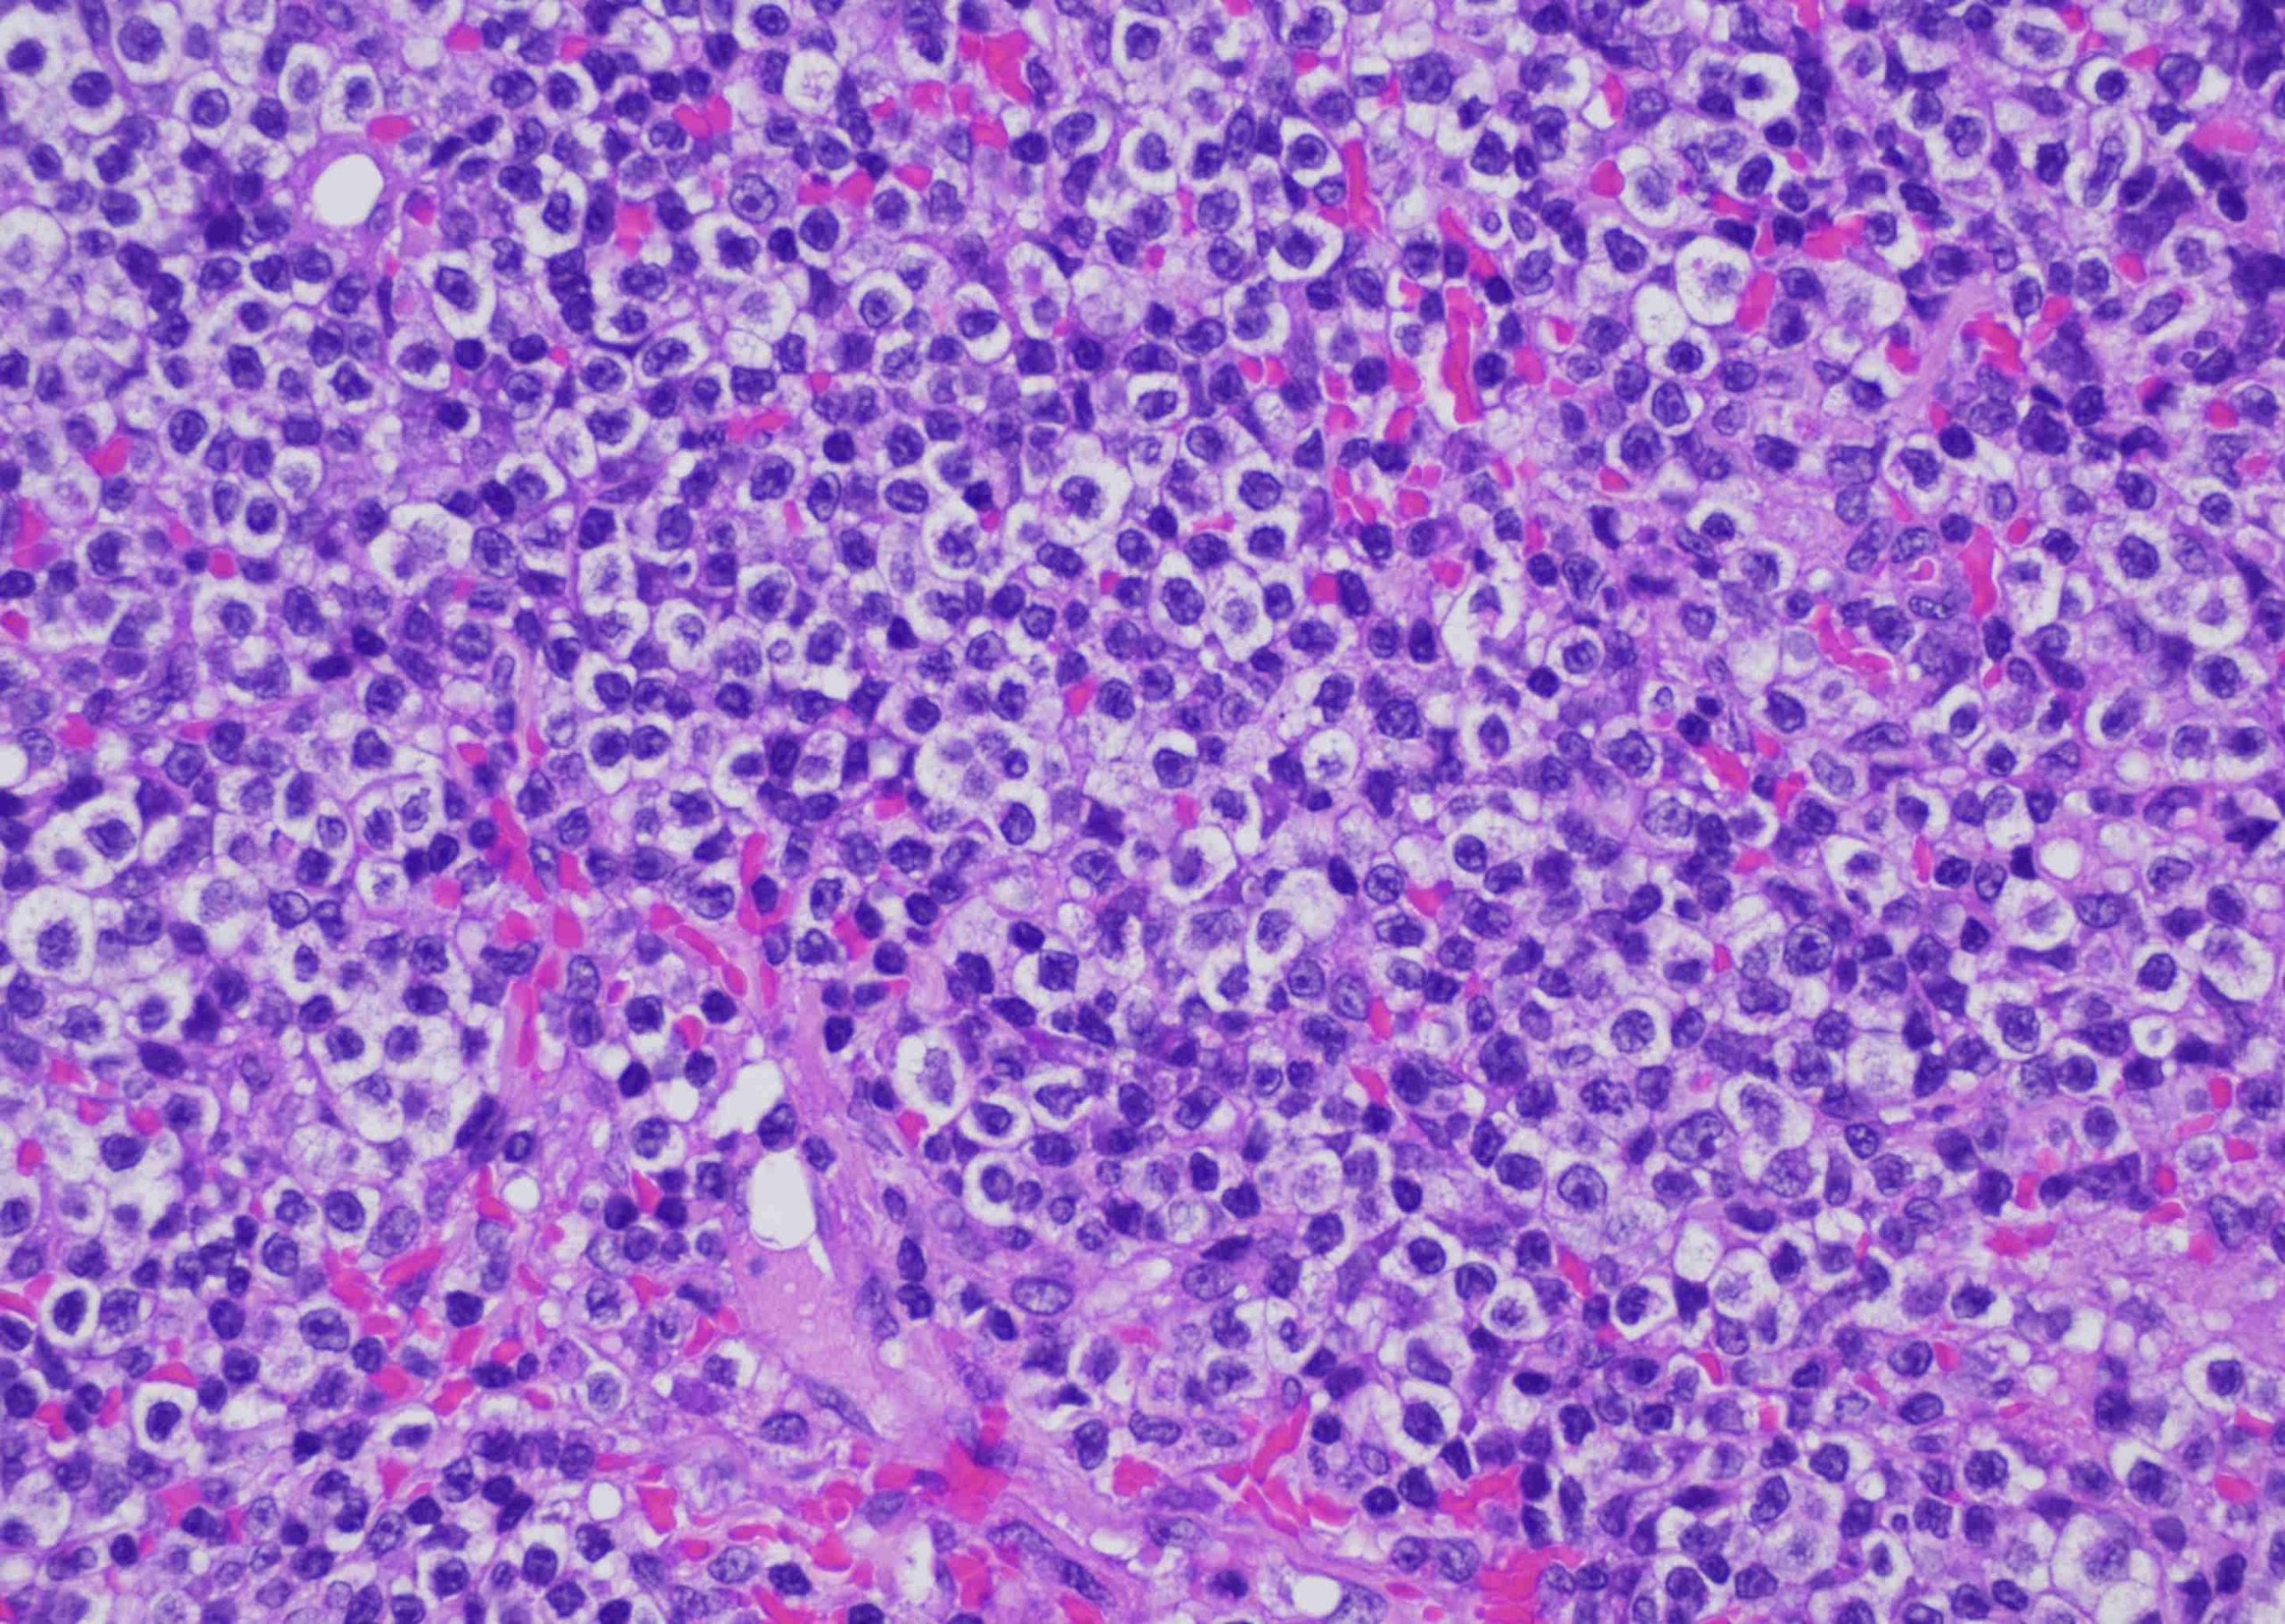

凄い数のリンパ球が出現しています・・・。

ただの炎症だと良かったのですが、予想通り「上皮向性リンパ腫」でした。これは表皮に限定して増殖するリンパ腫です。そうすると命には影響が少なそうなのですが、大多数のヒトの上皮向性リンパ腫と違って、犬は非常に予後が悪いです。これはヒトでは非常に悪性なグループに分類されるタイプが犬の主流のタイプだからです。

通常老齢のイヌが多く罹患します。更にやっかいなのは病期により非常に多様な症状を見せる事です。なので本当に単なる皮膚炎にしか見えない場合もあります。全身のかゆみを伴う紅斑および落屑が目立つタイプもありますし

単発あるいは多発の局面や結節の形成をするものもあります。

そして、この子の様に粘膜皮膚の紅斑、浸潤、色素脱、潰瘍浸潤性を起こす場合もあります。特に色素が抜けるのは大切な特徴です。皮膚炎であれば普通は炎症が起きると色素沈着が続発する方が多いです